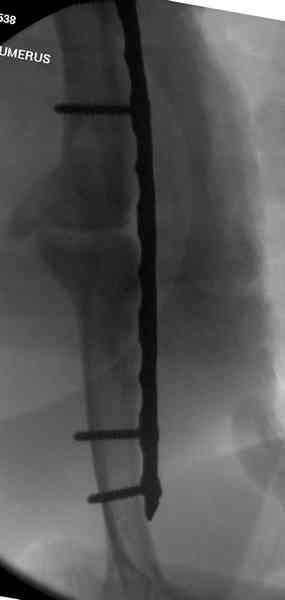

Первичную пластину убрали недели 6 назад из переднего оригинального доступа, и из-за подозрительности тканей вокруг пластины, решили провести реконструкцию поэтапно.

После промывки и дебридмента для уверенности уложили антибиотический цемент. Культура из раны в последующем была отрицательная.

Хотя сам не стороннник применения более массивных

имплантов для плеча, но для этого случая сделали

исключение. На снимке 4А диаметр мягких ткани около 20 см, при весе больной более 135 кг, и также выступление Андрея Волны подстегнуло к применению более массивной 4.5 мм локинг пластины.

Биологические стимуляторы типа Synthes chronOS мы

применяем только для закрытия дефекта в закрытом

пространстве, например в тибиал плато, пилоне и

ацетабулярных переломах.

Несмотря на то, что компания рекомендует, что препарат является остеоиндуктивным, но мы считаем, что препарат надо применять для заполнения дефектов, потому что "indicated for use in bony voids or gaps that are not intrinsic to the stability of the bony structure.

chronOS is indicated for use treatment of bony defects created surgically or through traumatic injury".

А для стимулирования мы применили массу из состава:

OP1 с деминерализованной костью, добавив к ним еще

красную часть, приготовленную из крови больной.

Взятая перед операцией кровь в количестве 80 мл

провели через центрифугу и без сывороточной части

красную матрицу добавили к остальным.

С такой массой наверное ложный сустав "over killed", но надеюсь, что-то из них при такой фиксации окажет стимулирующее действие.